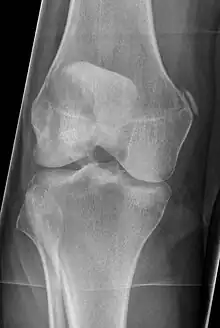

Diagnosis is typically made on radiographs demonstrating the Pellegrini-Stieda syndrome sign accompanied by pain or restriction of range-of-motion of the knee joint.[2] Pellegrini-Stieda syndrome sign is typically described by a longitudinally linear opacity, which is a process that is describes characteristic of calcification in the soft tissue located medial to the medial femoral condyle.[2] This calcification seen on imaging represents the ossification of the medial collateral ligament, which typically does not develop until approximately three weeks after the initial injury.[2]It is important to note to distinguish this radiographic finding from that of a medial femoral condyle avulsion fracture, which is an injury in which a pulling force of a tendon or ligament fractures away a piece of the bone from its attachment site.[2]

Pellegrini–Stieda syndrome (also called Stieda disease and Köhler–Pellegrini–Stieda disease) is the ossification of the superior part of the medial collateral ligament of the knee. It is a common incidental finding on knee radiographs. It is named for the Italian surgeon A. Pellegrini (b. 1877) and the German surgeon A. Stieda (1869–1945).[1] While the eponym refers to Pellegrini and Stieda, the condition was first discovered by Köhler in 1903, before any namesakes. Pellegrini-Stieda combines the aforementioned radiographic findings and concomitant medial knee joint pain or restricted range of motion.[2]